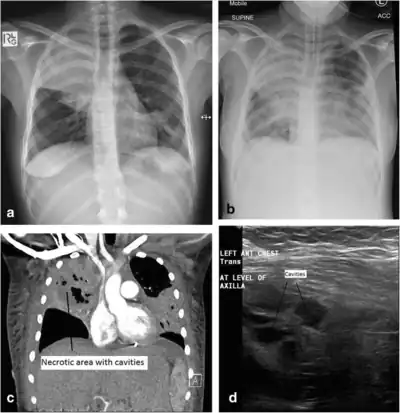

Additional imaging

a) Initial plain chest radiograph showing a dense right upper zone airspace opacity and lingula airspace changes, consistent with multi-focal pneumonia. The following images were performed 24 h later. b) Plain chest radiograph with the patient intubated and ventilated revealing cavitation in the right mid to upper zones, pleural effusion and more general airspace changes bilaterally. c) Computed tomography (CT) scan, coronal view, demonstrating non-enhancing area (necrotic) thin-walled cavities within the right upper lobe and lingula. d) Lung ultrasonographic image displaying thin-walled cavities in the lingula region of the left lung. This requires further clarification.[note 1]